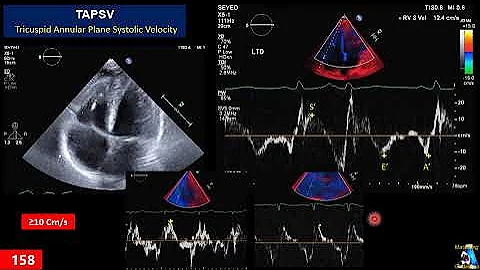

Cardiac Pocus Part 2: Techniques For Assessing Right Ventricular Function

Book a 1-on-1 Clarius demo: https://clarius.com/getdemo In this 1-hour webinar, you will learn to quickly and accurately use ...